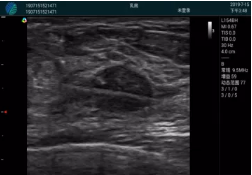

清晰顯示腺體內(nèi)低回聲快影,邊界清晰,包膜較光滑

確定進(jìn)針路徑并實(shí)時(shí)監(jiān)測抽吸針與腫塊位置關(guān)系

抽吸針進(jìn)入腫塊內(nèi)部進(jìn)行旋切

抽吸過程中可見腫塊明顯縮小,并根據(jù)腫塊位置改變針道位置

抽吸旋切后再進(jìn)行超聲復(fù)查,原腫塊區(qū)域未見殘留組織及出血